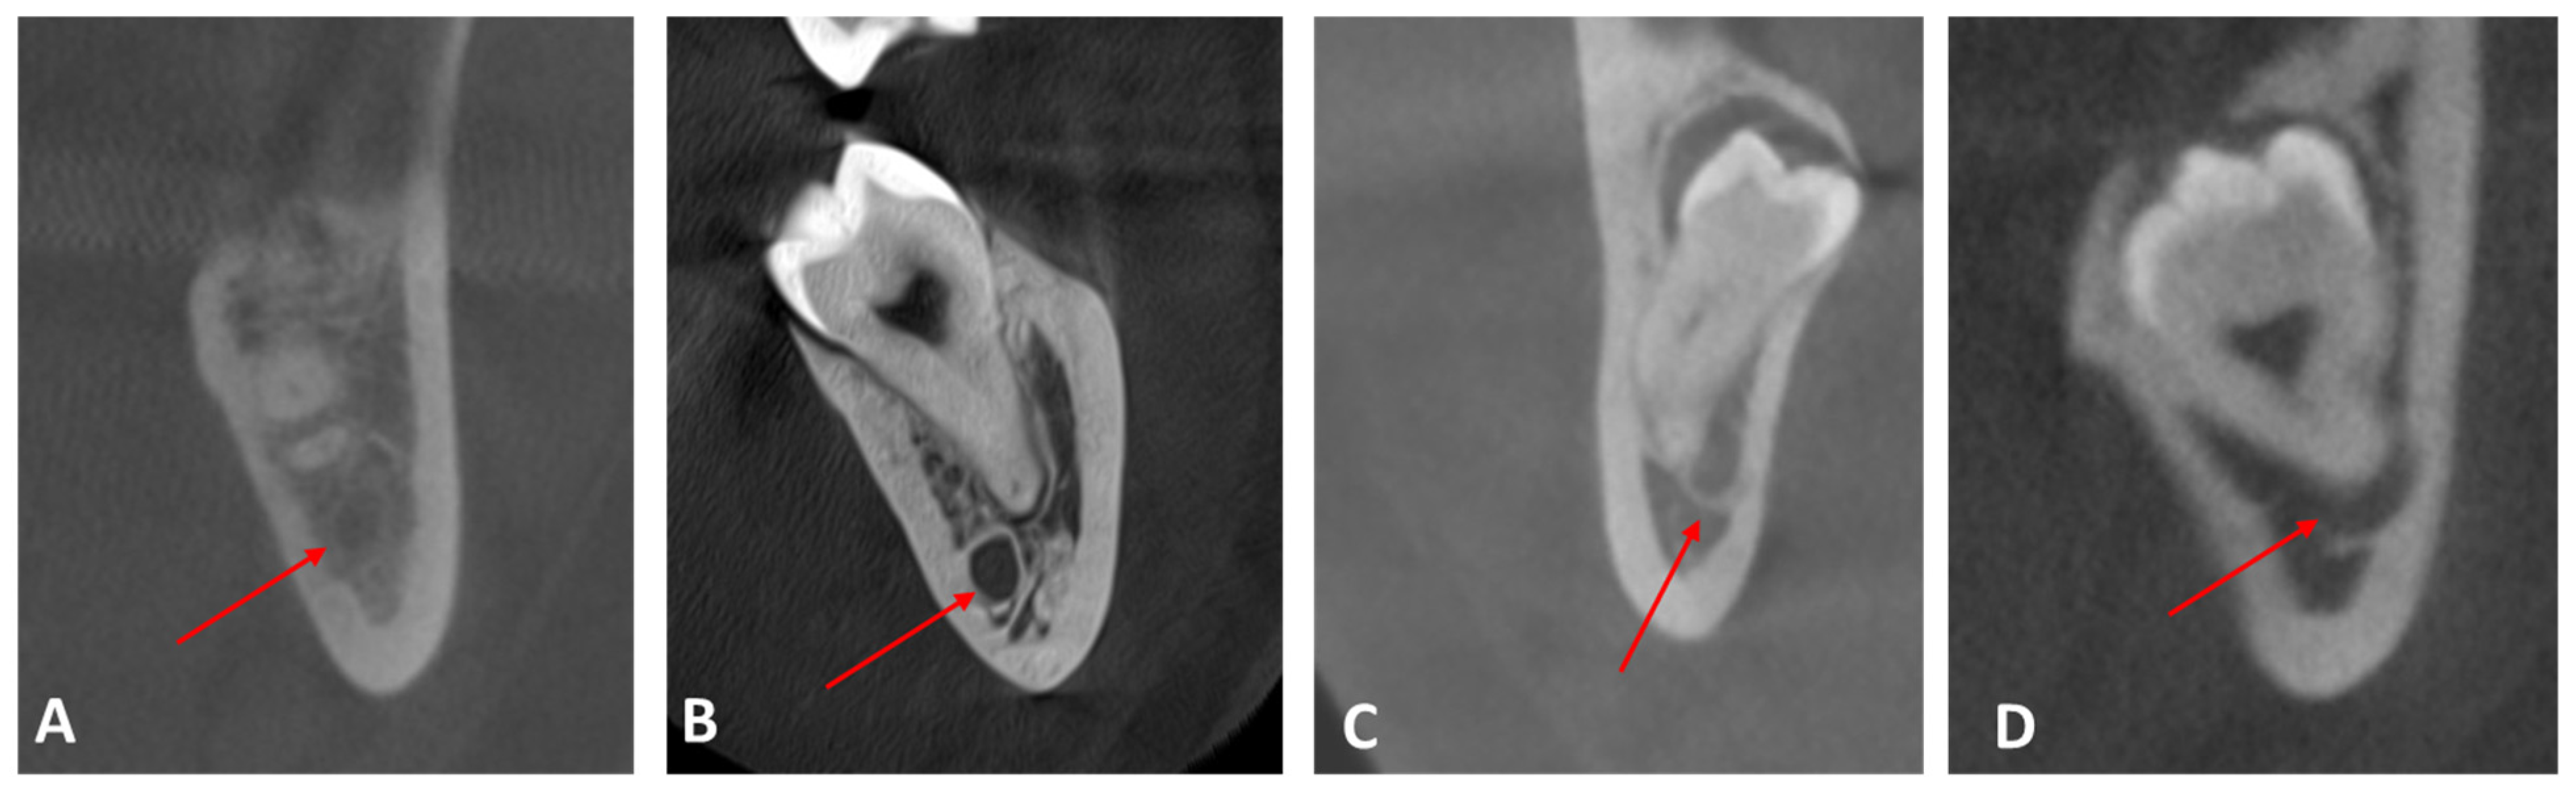

| Class I: the mandibular canal locates on the apical side | 179 | 70.8 |

| Class II: the mandibular canal locates on the buccal side | 44 | 17.4 |

| Class III: the mandibular canal locates on the lingual side | 21 | 8.3 |

| Class IV: the mandibular canal locates between the roots | 9 | 3.6 |